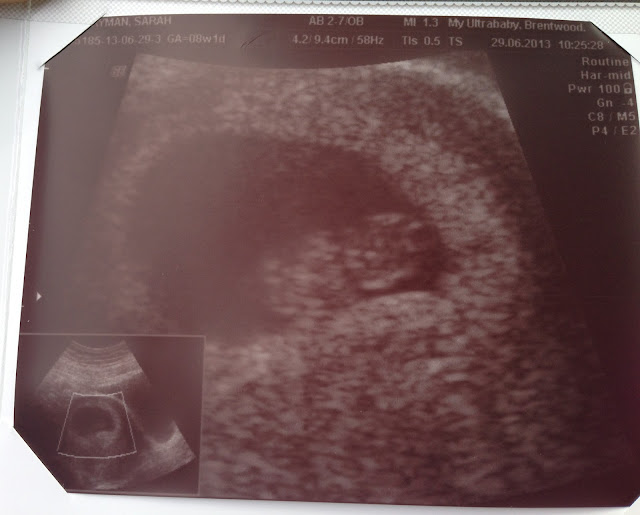

I'm so incredibly happy! On Saturday me and the Mr saw our little bean for the first time, and it was AMAZING!

I didn't know what to expect given that I've  never been pregnant before, but it was a lovely experience that was over just a little bit too quickly!

We were led into a large room, complete with sofas sporting pink and blue cushions (original) and I lay down on the chair-bed while gel was squidged on my swollen tummy.

At this point I was terrified they wouldn't find anything, then all of a sudden, out of the abyss, I saw a circular black, circle like thing appear on the screen, and within it, the most beautiful, tiny bean, complete with tiny arm and leg buds and a strong, fast heartbeat!

I chocked, I'll admit it, but it was AMAZING!

There was something there, there was a teenie tiny baby in my belly and I felt a huge rush of emotions and love for this tiny person growing inside me.

I had to hold my breath while the sonographer held the wand over my beans heart to check his/her heart rate as with each breath I took she lost the spot over the baby (He/she is super tiny right now after all!)

My bean's heart was pumping away at 175 beats per minute! Incredible.

Going by the first day of my last period I had been dated at 8+1 weeks the date of the scan, but the sonographer revealed that I was a few days ahead at 8+4 or 5 weeks, though that would probably change at the more accurate 12 weeks scan.

It was an amazing experience; So reassuring and incredible and I can't wait to see my little bean again in a few weeks!